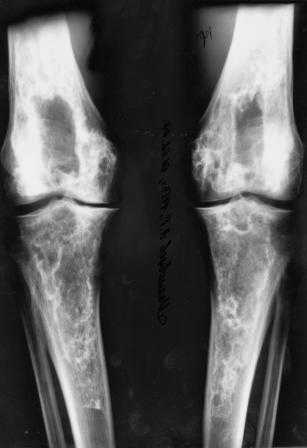

Мужчина, 53 года, жалуется на постоянные ноющие боли в костях голеней, усиливающиеся после ходьбы, боли в коленных суставах. Считает себя больным с 1987 г., когда впервые появились боли в коленных суставах. В 1990 г. выставлен д-з: вторичный ДОА коленных суставов, фиброзная дисплазия костей. После проведенного лечения (НПВП, радоновые ванны, курс введения кислорода в коленные суставы) в течение 5 лет ремиссия. С 1995 г. ежегодные обострения весной и осенью, проявляющиеся болями в коленных суставах, явлениями синовита. Проводилось лечение НПВП, физиопроцедуры, внутрисуставное введение дипроспана с положительным эффектом. С 2004 г. - эффекта от проводимой терапии нет. В 2006 г. впервые по рентгеновским снимкам выставлен д-з: болезнь Альберса-Шенберга. Деформирующий гонартроз справа 2 ст., слева 3 ст. С 2006 г. ездит на лечение в Китай, где проводится лечение радоновыми грязями, массаж с положительным эффектом. Объективно: коленные суставы деформированы, при пальпации б/болезненные. Движения в полном объеме. При ходьбе хромает. Диагноз: болезнь Алберс-Шонберга. Деформирующий гонартроз справа 2 ст., слева 3 ст.Хотелось бы уточнить диагноз и определить тактику дальнейшего лечения. Заранее спасибо.

Представленные Вами данные о пациенте 57 дет с болезнью Альбертс-Шенберга чрезвычайно интересны, но диагноз вызывает большие сомнения. Для мраморной болезни характерно прееобладание склероза, а на представленных рентгенограммах преобладает симметричная дезорганизация архитектоники губчатой кости в эпиметафизарной зоне дистальных отделов бедер и голеней.

Уважаемый Константин Иванович! Полностью согласен с проф. Михайловым, данный случай не похож на мраморную болезнь, при которой имеется резкое, строго симметричное и генерализованное уплотнение костной ткани (остеопетроз), и кость оказывается построенной преимущественно из гомогенного компактного костного вещества. Для примера привожу случай из архива нашего института (бедренные, плечевые кости и таз, рис 1,2,3)

Изменения структуры костей у Вашего пациента больше похожи на полиоссальную форму фиброзной дисплазии или болезнь Педжета, возможены также инфаркты костного мозга б.берцовых костей. К сожалению, качество снимка не очень хорошее, непонятно, сохранен ли кортикальный слой б.берцовых костей по передней поверхности.